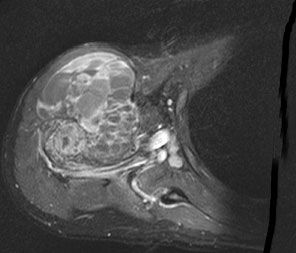

| Diagnostik | MRT- Bild eines Osteosarkoms des Humerus![]()  | ||